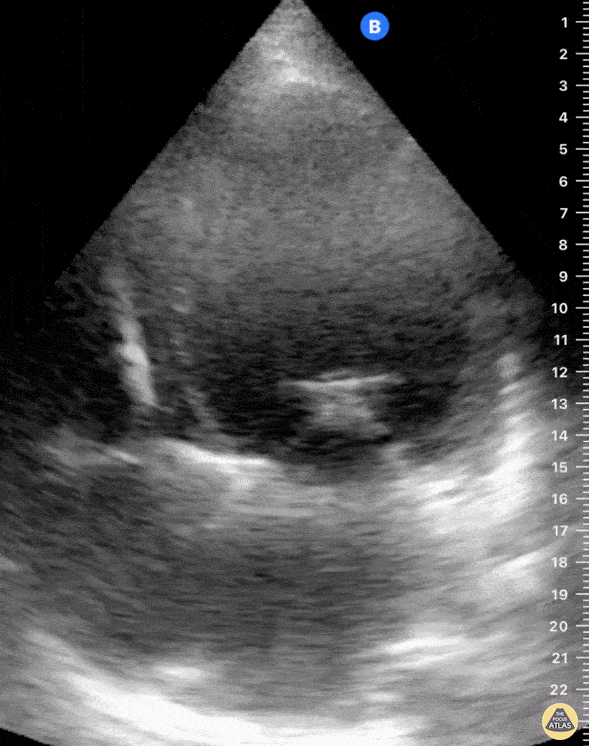

A 54-year-old man with history of dilated cardiomyopathy on maximum tolerated doses of guideline directed medical therapy and implantable cardioverter defibrillator presented with progressively worsening dyspnea with minimal activity. Transthoracic ultrasonography showed evidence of severe functional mitral regurgitation for which he underwent mitral clip placement (seen here). This point of care ultrasound was obtained during a clinic follow up when he reported sustained resolution of symptoms; there was also no appreciable mitral regurgitant jet on color doppler. Shahad Al Chalaby, MD (PGY3) @shahad_Chalaby Alameda Health System Internal Medicine Residency Program Oakland, California